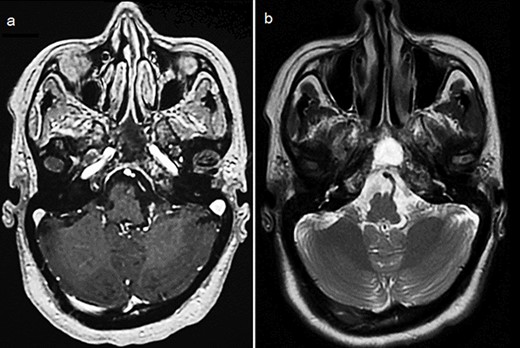

By the end of biological exploration, the patient reported a recurrence of headaches and blurred vision, 2 months after surgical decompression. Cerebral MRI revealed a relapse of the sphenoid plasmacytoma, measuring 70 mm (Fig. 3). Given the pathological diagnostic result, surgical re-intervention was not decided. Instead, the patient was treated with external beam radiotherapy (RTX) focused on the sphenoid bone (30 Gy), followed by immunochemotherapy with zoledronic acid. After 6 months, complete response was noted with the resolution of symptoms, disappearance of the monoclonal band, normalization of sFLC, and persistence of lytic sequelae on cerebral MRI (Fig. 4). Autologous stem cell transplantation (ASCT) was successfully performed, and the patient was put under treatment maintenance. After 18 months of follow-up, clinical, biological, and radiological evaluation confirmed sustained complete remission.

Cerebral MRI (axial views) showing a relapse of the sphenoid BP measuring 70 mm (a, b: T1 weighted post-gadolinium; c: T2 weighted).

Control cerebral MRI (axial views) showing the disappearance of the sphenoid BP after treatment with RTX and immunochemotherapy. (a: T1-weighted; b: T2-weighted).